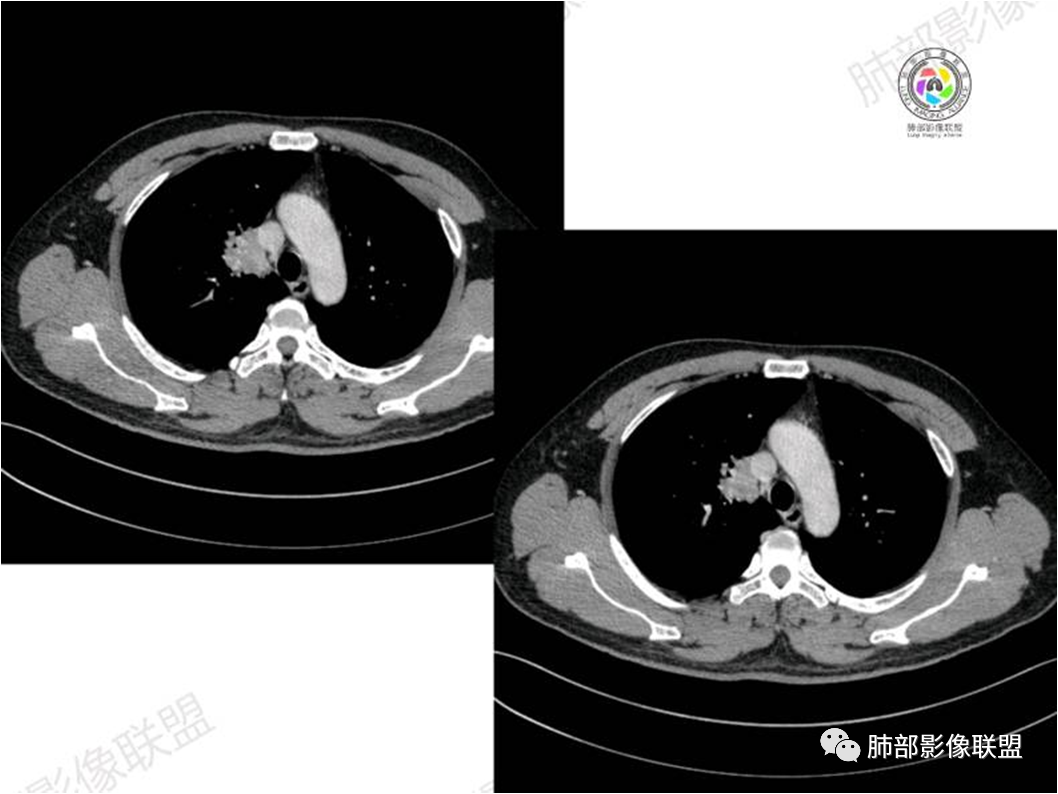

病灶紧贴纵隔胸膜

糊墙,胸膜外未见明显侵犯迹象

病灶整体狭长一些

边缘平直、凹陷为主

支气管外侧带的通畅,片内侧带的似乎中近端狭窄,堵塞

内部肺动脉走形还可以

近端支气管壁弥漫增厚

强化均匀

整体炎性的特点比较明显

不踏实的地方:

边上有些毛糙

恶性待排除

恶性:还是淋巴瘤多见一些。